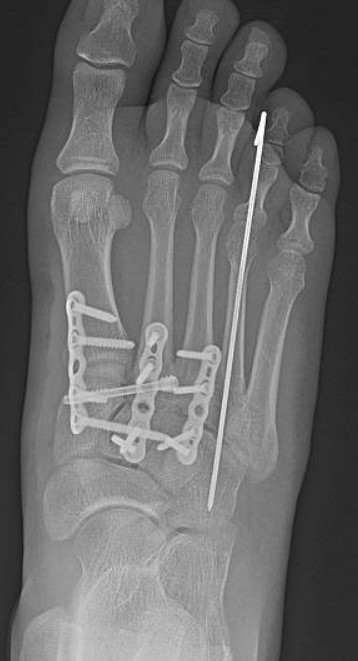

education. While he practices all aspects of foot and ankle surgery, he has made especially significant contributions in advancing our understanding of charcot arthropathy and Lisfranc injuries.